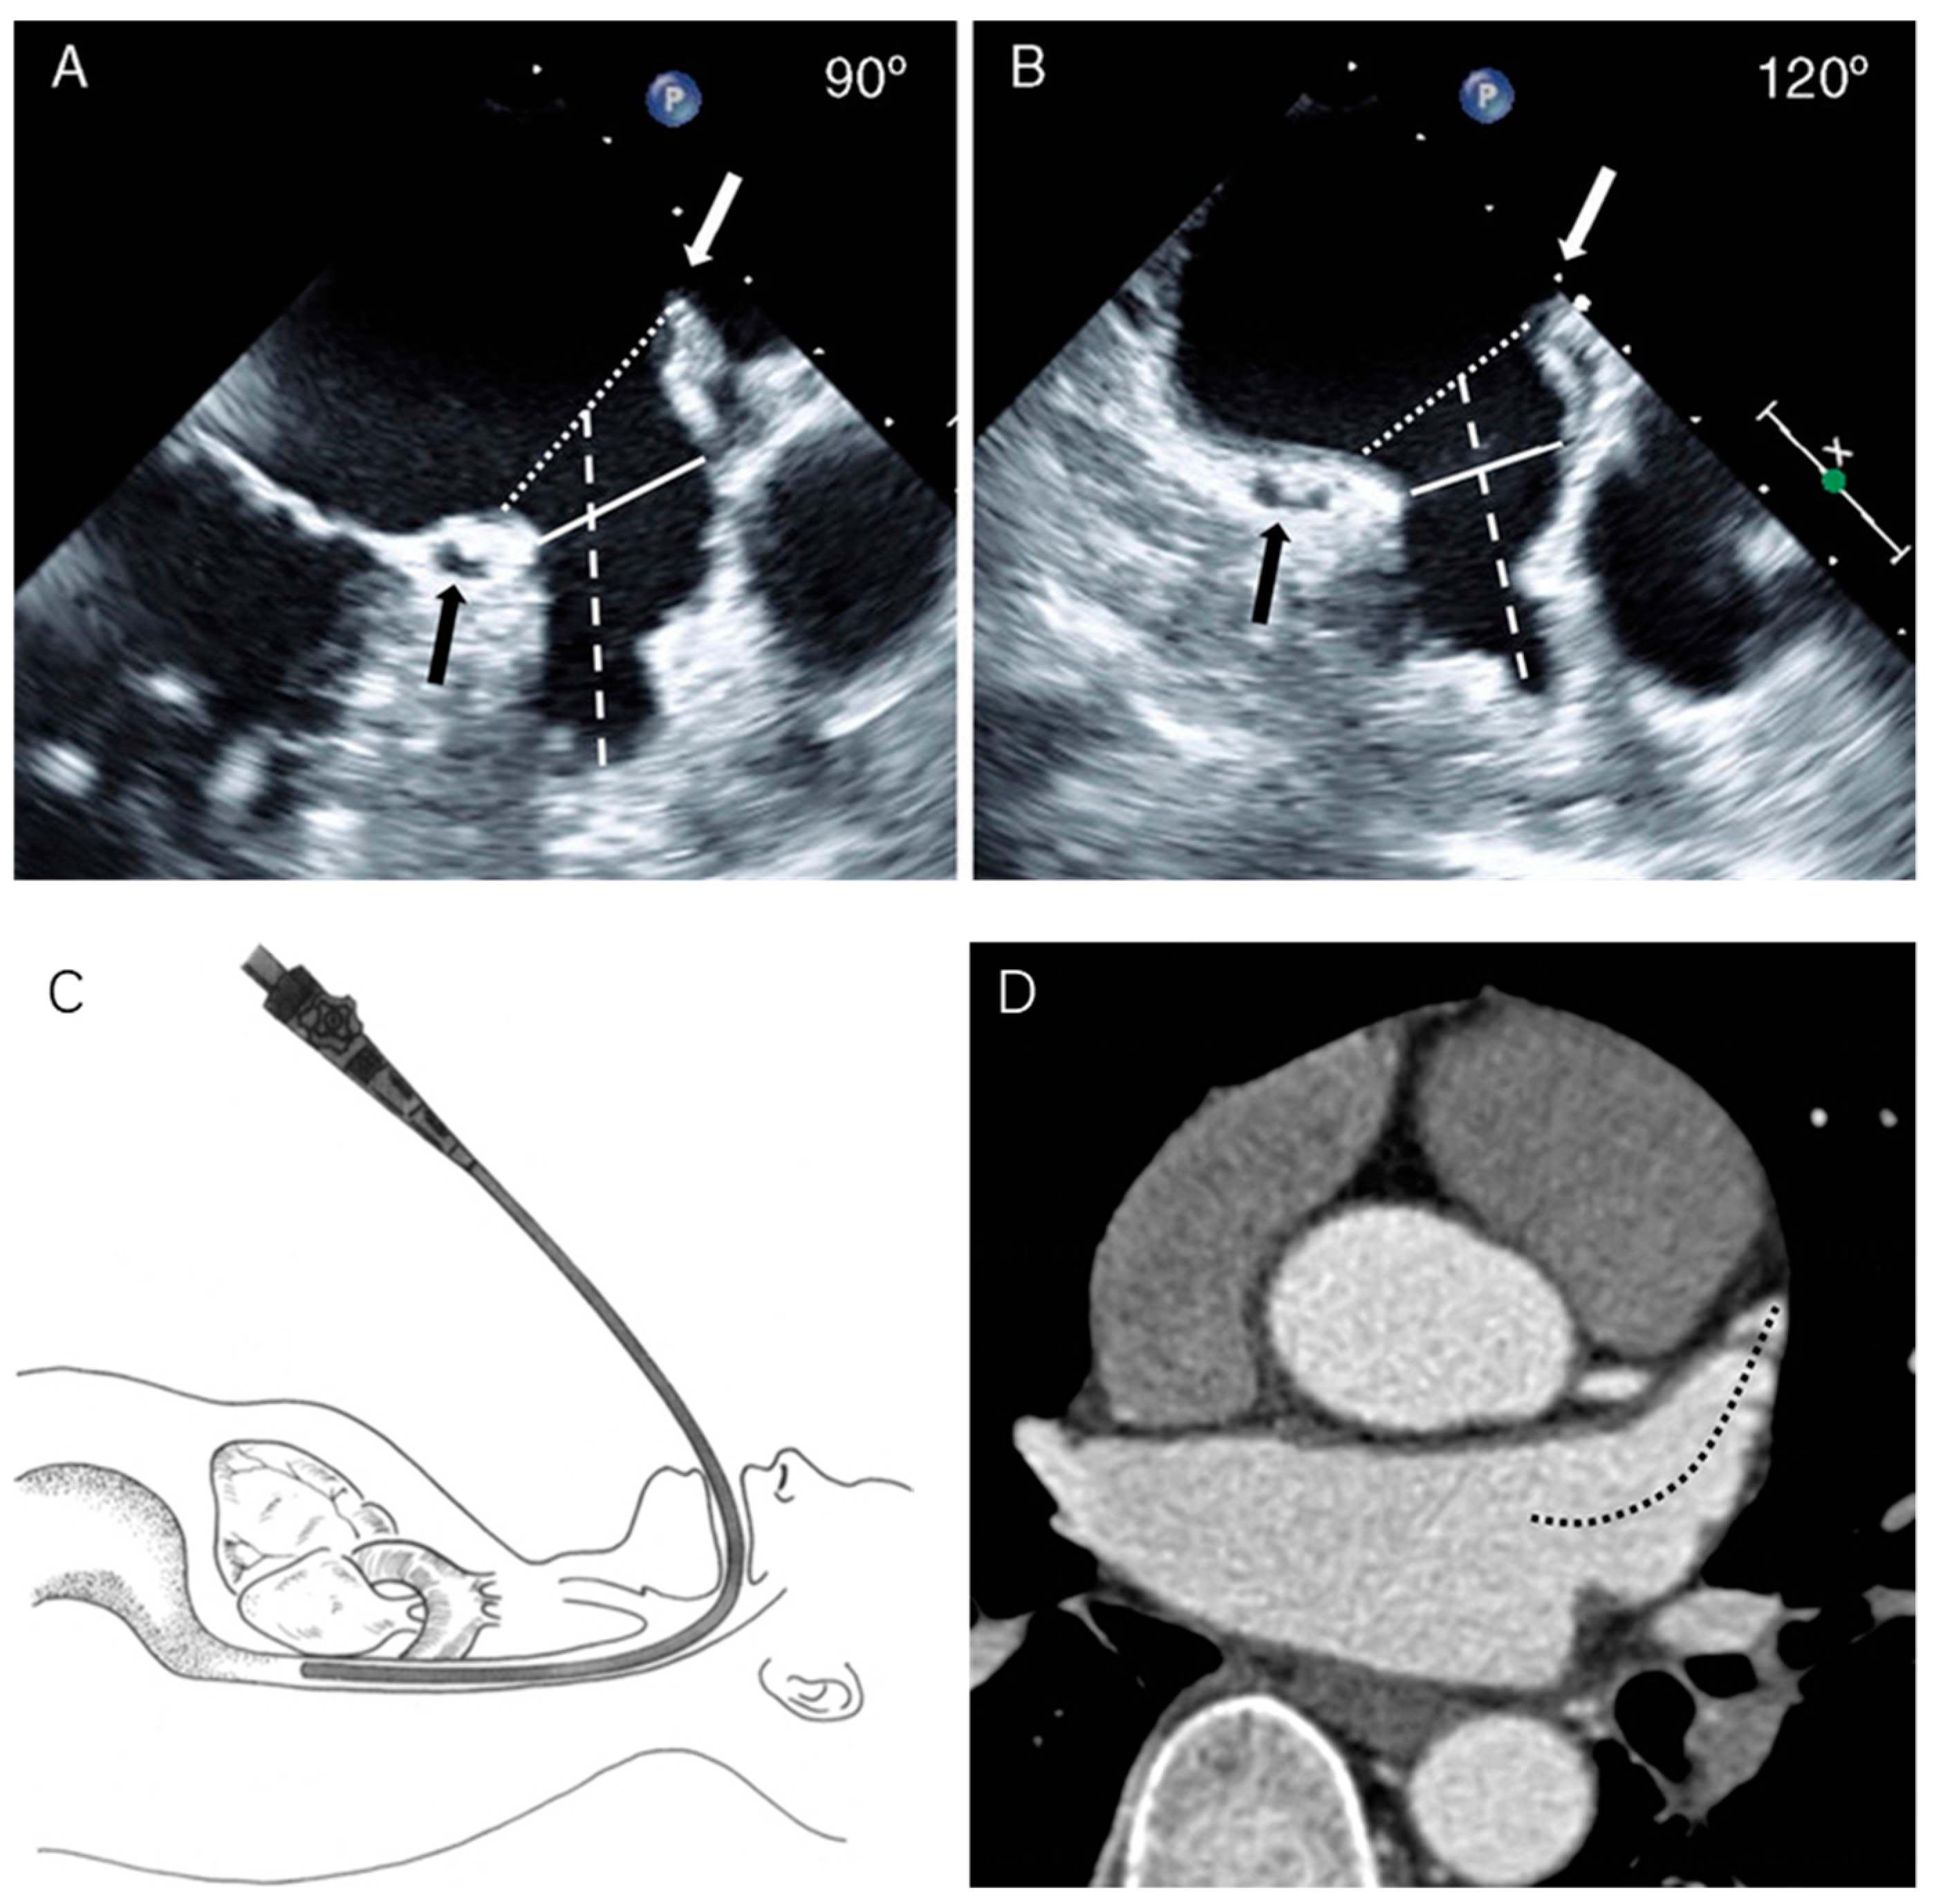

5.1.1. Transesophageal Echocardiography

5.1.2. Intracardiac Echocardiography (ICE)